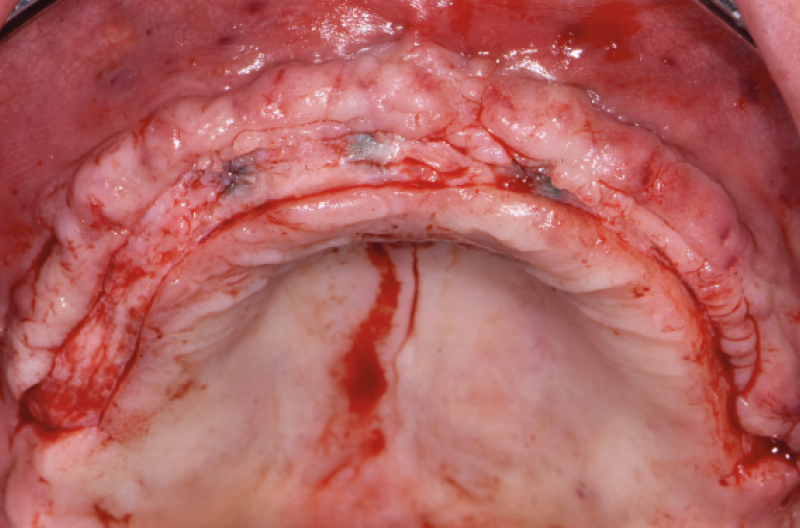

Ho riaperto il mascellare superiore con un lembo a spessore parziale palatino e con scarichi solo distali per limitare al minimo il trauma allŌĆÖosso perimplantare; dopodich├® ho scelto i monconi MUA pi├╣ idonei, tutti GH 1,5 mm uno diritto, tre angolati a 15┬░ e due angolati a 25┬░. Una volta parallelizzati, ho attivato i monconi MUA negli impianti e avvitato gli adattori Conic per trasformarli in monconi MUA-Conic. Dopo aver suturato il lembo, ho attivato le cappette Fixed sui monconi MUA-Conic e poi si ├© proceduto alla ribasatura della protesi opportunamente scaricata in corrispondenza dei monconi MUA-Conic. Durante la procedura intraorale di inglobamento delle cappette Fixed, la protesi si ├© autocentrata in occlusione con la protesi conometrica fissa provvisoria inferiore. Infine la protesi ├© stata rifinita, riposizionata in bocca e attivata (Figg. 30-37). A distanza di un mese entrambe le Toronto provvisorie sono state rimosse e ribasate per un migliore condizionamento del tessuto gengivale (Fig. 38).

Fig. 30 – Riapertura del superiore con lembo a spessore parziale